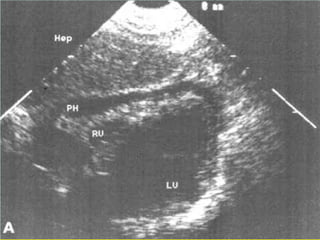

• Investigations : FAST , DPL , CT , Angiogram

3. Investigations

* pelvic film : AP , Inlet , Outlet , Judet

* FAST

* DPL

* CT scan

* Angiography